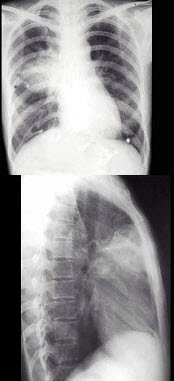

14、单项选择题

男,65岁,咳嗽,右胸痛,痰中带血丝1周。胸部后前位片示:右肺门影增大,右上肺大片状致密影,水平裂呈反“S”样改变。

右上肺大片状致密影侧位片位于()

A.右肺上叶尖后段

B.右肺上叶前段

C.右肺下叶背段

D.右肺中叶

E.右肺上叶

15、单项选择题 关于右肺上叶不张的X线表现,错误的是()

A.右上叶呈密度增加的大片阴影

B.肺不张叶向上移位

C.气管可向右侧移位

D.右中下叶呈代偿性肺气肿

E.右肺门的阴影向下移位